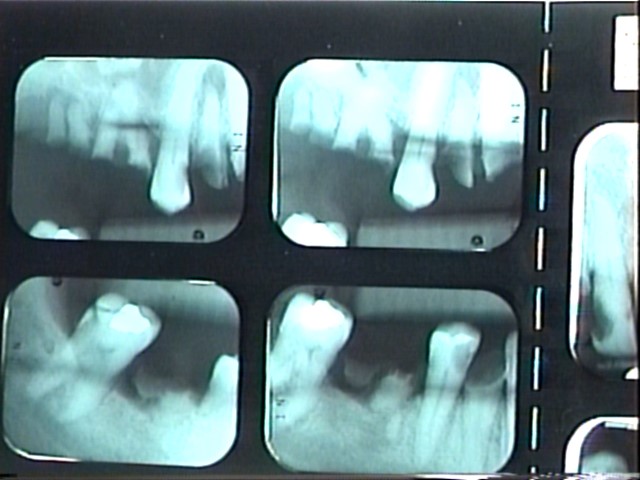

The patient in Figure 10 through Figure 12 was pregnant when she presented for dental treatment. The pregnancy was unplanned and she had had a lack of prenatal care. Continuing meth use during the pregnancy resulted in a positive toxic baby. She stated that she had just stopped using meth and had entered a rehabilitation facility a few days before. She was brought to the author’s clinic with a toothache. Note that as seen in these images, extreme accumulation of plaque, lack of oral hygiene, and severely decayed and missing teeth are classic manifestations in meth users.

Fig 12. Radiographs of patient in Fig 10 and Fig 11 illustrating nonrestorability of the dentition.

Figure 12